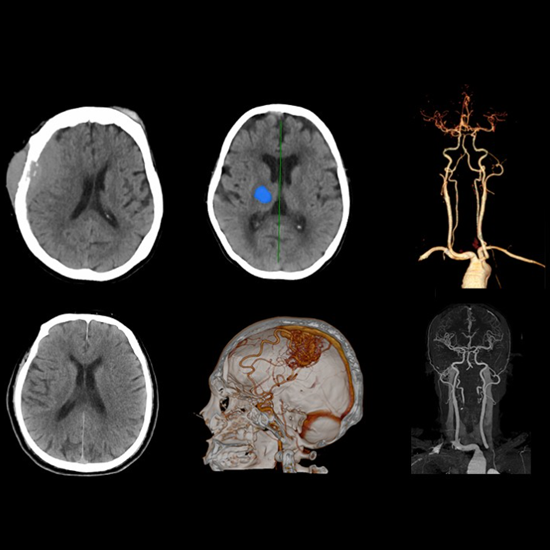

Anatom 64 Clarity, kardiyak görüntülemede giriş seviyesindeki rakiplerine oranla daha düşük doz ile daha yüksek kaliteli görüntüler sunan teknolojik donanımlara sahip 64 kesit bir bilgisayarlı tomografi sistemidir.

Yüksek zamansal çözünürlük sunarak kullanıcı deneyimini iyileştiren Anatom 64 Clarity, aynı zamanda 5.3 MHU'luk tüpü sayesinde 120 saniyeye kadar devamlı çekim imkanı sunar ve tüm gün çekimlerde herhangi bir sorun yaşanmamasına olanak tanır.

Görüntü bozulmalarını engelleyecek yazılımlara sahip olan Anatom 64 Clarity, farklı klinik ihtiyaçlara uyum sağlayabilmesi için dijital ve mekanik eğim ayarlarına sahiptir ve gerçek zamanlı çarpışma önleme sistemleriyle hasta güvenliğini de sağlar.